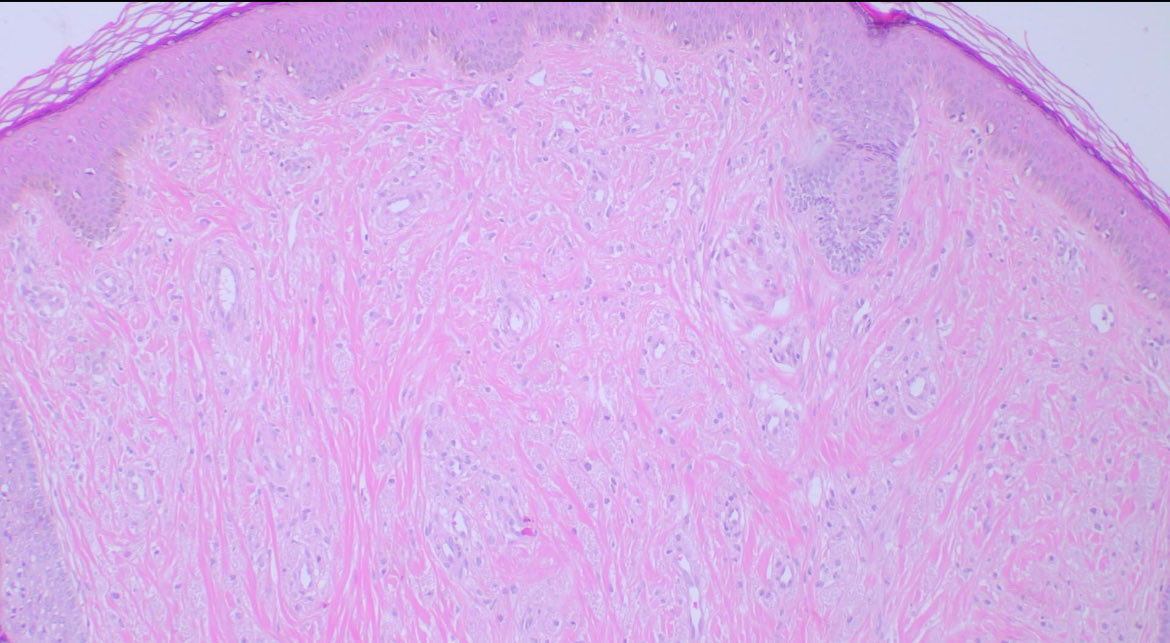

Non-neural granular cell tumor Intradermal tumor with cells showing granular cytoplasm. S100 and Sox10: negative HE, CD68, CD56 #path #pathology #dermtwitter #dermatology